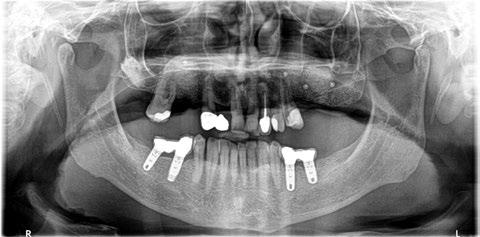

Figura 16. Ortopantomografía postoperatoria.

Figura 2. Ortopantomografía inicial.

Figura 27. Ortopantomografía del provisional atornillado en boca para verificar ajuste.

ortopantomografía de verificación del ajuste pasivo de todos los implantes. Por último, tapamos las chimeneas con teflón y resina provisional y se chequeó nuevamente la oclusión, dando nuevamente las instrucciones de higiene y mantenimiento de la prótesis provisional (Figuras 24-27).